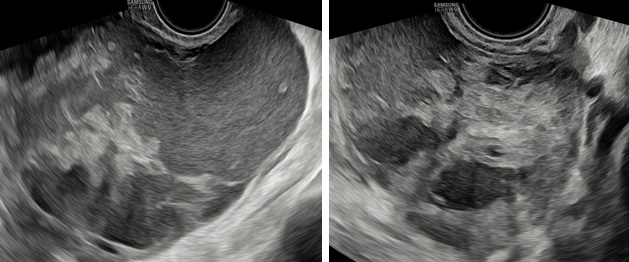

Hình 2: Mặt cắt dọc và ngang qua ngã âm đạo thấy khối u có phản âm hỗn hợp, bên trong có nhiều mảng phản âm dày, di động khi di chuyển đầu dò, giúp hướng đến bản chất xuất huyết.

– Siêu âm: Tử cung và 2 buồng trứng bình thường. Ở cùng đồ sau có cấu trúc echo kém không đồng nhất dạng hình ống, có vách ngăn dày thông nhau, kích thước # 84x 89x 37 mm, bờ trong thành u không trơn láng, bên trong có nhiều mảng echo kém dạng mô đặc, tăng sinh mạch máu mức độ 2. Bụng và cùng đồ: không dịch.

– Chẩn đoán siêu âm: Huyết tụ thành nang. Chẩn đoán khác: áp xe phần phụ.

Hình 3: Siêu âm ngã bụng thang xám cắt dọc và ngang cho thấy khối u nằm mặt sau tử cung lan qua hai bên hố chậu.

Hình 4: Siêu âm ngã âm đạo thang xám cho thấy khối u hình ống ở cùng đồ sau nhiều vách ngăn dày thông nhau.

Hình 5: Siêu âm ngã âm đạo cho thấy thành u có tăng sinh mạch máu độ 2